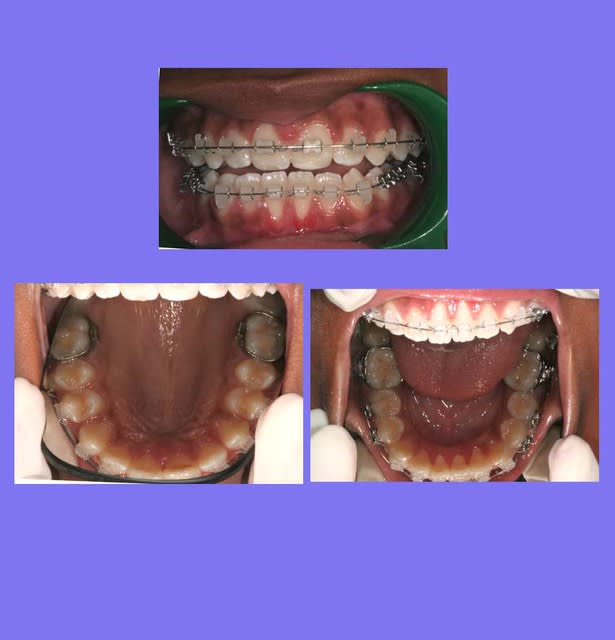

Voici le cas depuis le début, traité avec mes Bk. modifiés qui permettent de travailler en passif en début de traitement, en inter-actif au milieu de traitement, avec ou sans les ressorts de Root, et parfois en friction forte en fin de traitement pour les finitions

C’est un cas ancien ou je ne faisais pas assez de photos et ou j’essayais différentes marques de Bk.

Reprise du cas au départ

1°) Q.H. Sup pendant 6 mois, désolé, pas de photos

2°) Appareillage MB. Sup et 2 mois après Inf., avec mes Bk. modifiés en position Damon

On peut observer un décalage des points inter-incisifs et des rotations des Inc. Inf.

Voir Photo